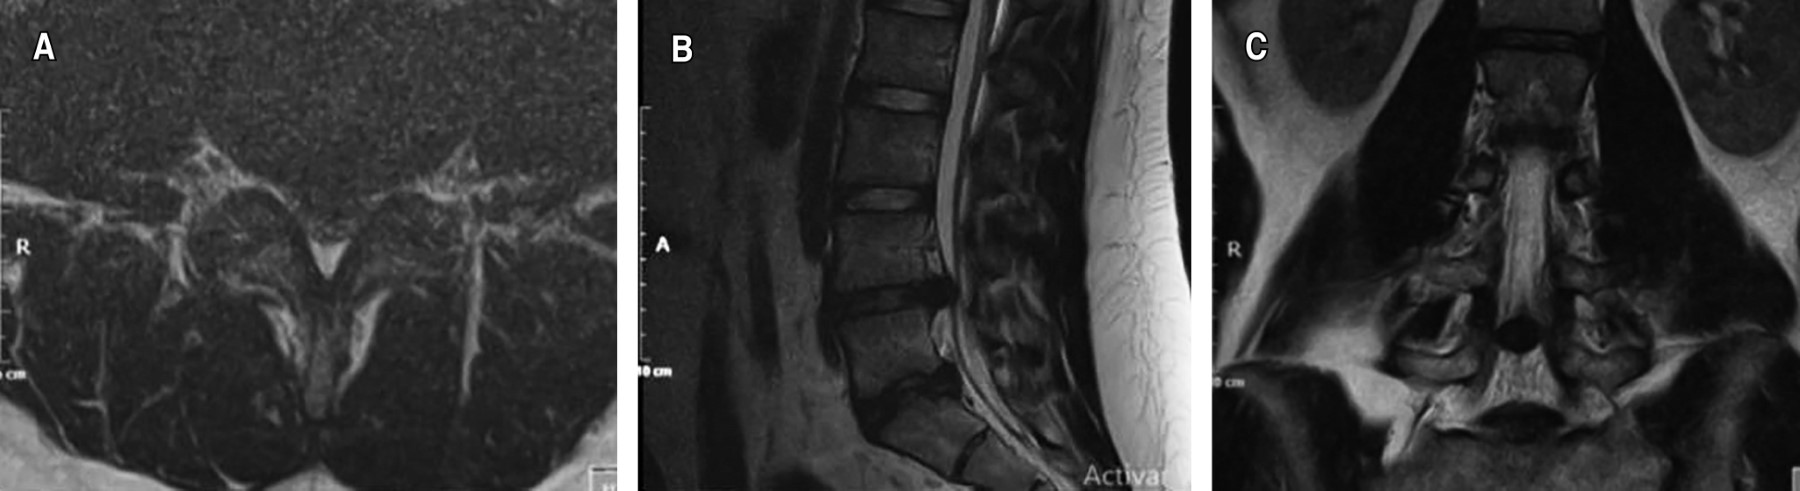

Figure 1